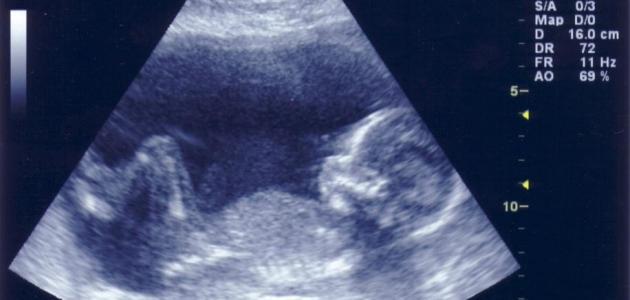

يسعى الوالدان وغيرهم من أفراد العائلة إلى التعرف على جنس المولود المنتظر بعد الشهر الرابع من الحمل، حيث تكون أعضاؤه التناسلية قد اكتمل نموها وأصبحت ظاهرة بشكل واضح، إلا أنه في كثير من الأحيان يعجز الطبيب المختص تحديد جنس الجنين من خلال فحص السونار حتى خلال الأشهر الأخيرة للحمل.

وغالباً ما يعود سبب ذلك إلى اتخاذ الجنين لوضعية تجعل من الصعب على الطبيب المختص الحصول على رؤية واضحة للأعضاء التناسلية للجنين، كما تتسبب بعض الوضعيات التي يتخذها الجنين في انعدام رؤية الأعضاء التناسلية بشكل كامل.

يعتبر فحص السونار من أفضل الطرق المتبعة لتحديد جنس الجنين بعد انقضاء المرحلة الأولى للحمل وأكثرها دقة، لذا تنصح الحوامل بتناول بعض أنواع الأطعمة التي تساعد في زيادة حركة الجنين قبل فحص السونار بفترة قصيرة، ومن أهمها الأطعمة الغنية بالسكريات، مثل الحلويات والشوكولاتة وغيرها من الفواكه الغنية بالسكر مثل العنب والتمر، كما يساعد شرب عصير الليمون المخفف بالماء مع رشة من الملح في تحفيز الجنين على التحرك والتقلب في رحم الأم.

يقوم الأطباء ببعض الإجراءات التي تدفع الجنين على الحركة في حال اتخاذه وضعية غير مناسبة خلال فحص السونار، ومن هذه الإجراءات الضغط على بطن الأم من جهات معينة حتى يشعر الجنين بالتضايق من الوضعية التي يتخذها ويبدأ بالحركة من أجل اتخاذ وضعية مريحة أكثر من السابقة، مما يمكن الطبيب المختص من رؤية الأعضاء التناسلية للجنين بشكل أوضح خلال تحركه، وبالتالي تحديد جنس الجنين.

يعتبر هذا الفحص من الفحوص الدقيقة التي تمنح الطبيب رؤية رباعية لجسم الجنين، وغالباً ما يستخدم هذا الفحص للكشف عن أي تشوهات خلقية أو أمراض لدى الجنين، ويمكن اللجوء إلى فحص أعضاء الجنين للكشف عن جنس الجنين في الحالات التي يعجز فحص السونار عن تقديم نتائج واضحة لجنس الجنين، إلا أنه نادراً ما يستخدم هذا الفحص في تحديد جنس الجنين بسبب تكلفته المرتفعة جداً مقارنةً مع تكلفة فحص السونار.